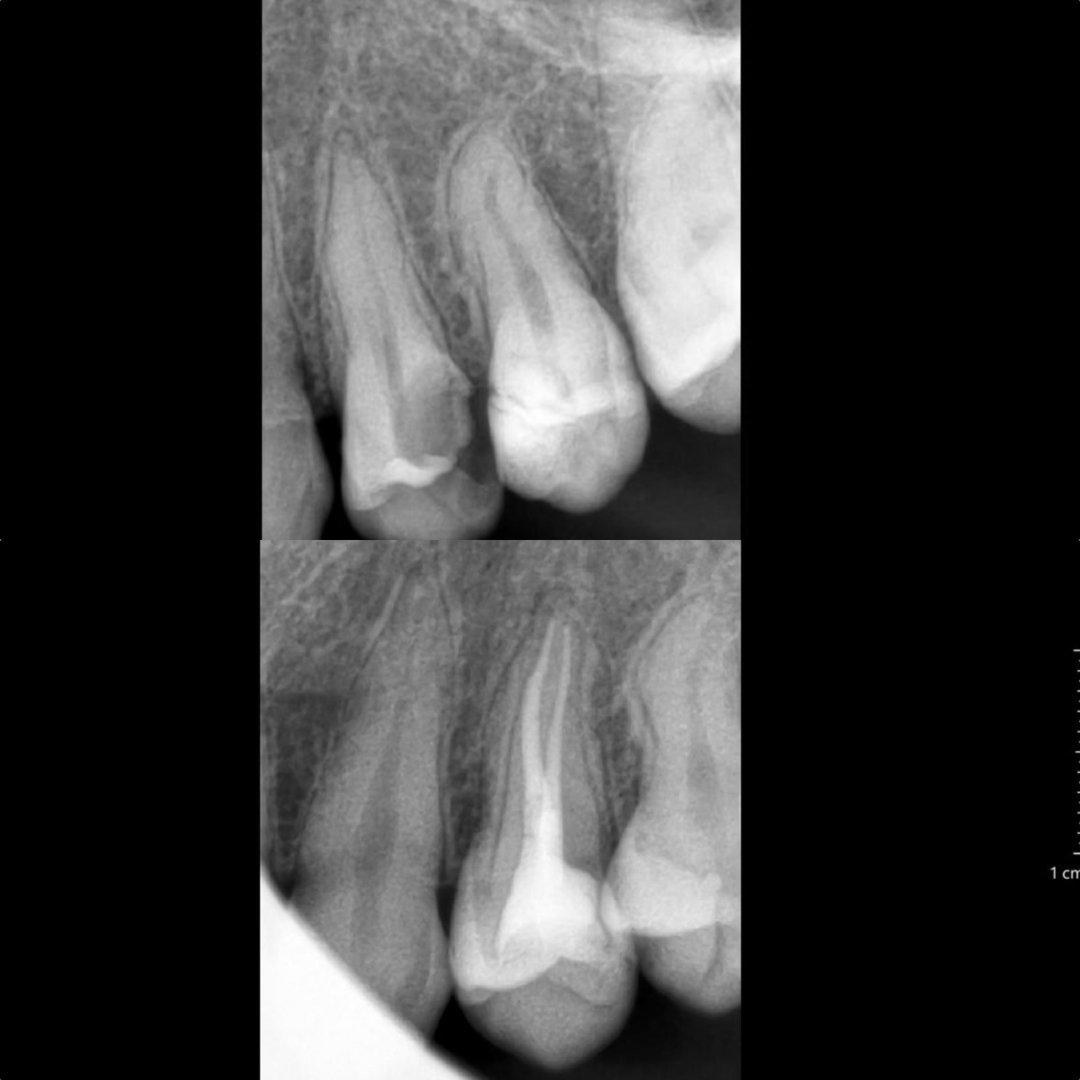

Before After Perawatan Saluran Akar (PSA) di Klinik Utama Pondok Gigi Jakarta

Transformasi nyata setelah perawatan saluran akar (PSA) di Klinik Utama Pondok Gigi Jakarta. Dari gigi rusak dan nyeri hingga kembali sehat dan berfungsi normal. Dikerjakan oleh dokter gigi profesional dengan teknik endodontik modern dan alat berteknologi tinggi untuk hasil maksimal.